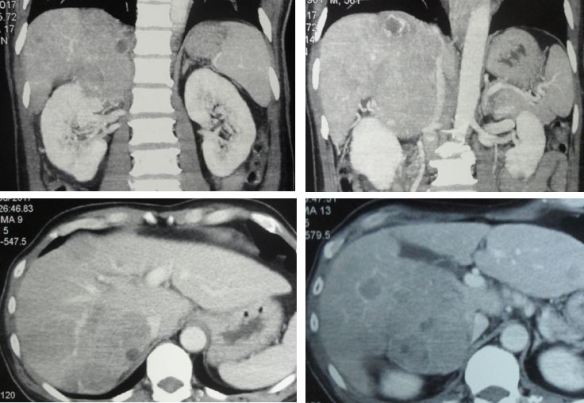

Surgery, Radiation and Chemo Did Not Cure Malignant Peripheral Nerve Sheath Tumour (Neurofibrosarcoma)

Alex (not real name) is 23 years old. He was born with a certain nerve disorder. His right arm had many benign lumps. When he was 11 years old, his right palm started to swell. He could not write with his right hand anymore.

Composite-1-Hand

Alex underwent a debulking surgery — the lumps were removed. He was told that it was not cancerous. Later in September 2013, there was a swelling in his right arm pit. The mass grew bigger and became painful.

Composite-2-Armpit

A CT scan in January 2014 indicated:

• A large axillary mass — malignancy needs to be considered. The right subclavian, axillary and brachial arteries pass above and lateral to this mass.

• No evidence of lung or mediastinal metastasis.

A true-cut biopsy was done and indicated:

• High grade spindle cell sarcoma favouring malignant peripheral nerve sheath tumour.

Alex underwent an operation to remove this entire right upper limb. Below is the surgeon’s note indicating the extensiveness of the surgery.

Alaister Lim scan

Histopathology confirmed a malignant peripheral nerve sheath tumour (T2bNoMo), Stage 3.

After the surgery Alex received 32 times of radiation treatment. There was no other medication.

Barely six months later, August 2014, the cancer spread to his lungs. Alex underwent 3 cycles of chemotherapy. The treatment was not effective. Alex again had more chemo — 12 cycles in all. The drugs used were Gemzar and Cisplatin.

lung--600

In February 2015, follow up examination showed:

• Mixed response of the lung nodules. Some nodules are smaller but some previously small ones are larger.

• A new nodule seen in the left upper lobe adjacent to the left 4th rib.

Chemotherapy did not help control his lung metastasis. Alex decided to give up medical treatment and came to seek our help.